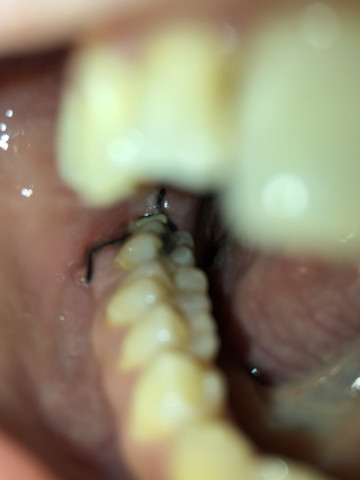

Ist Meine Wunde Nach Weisheitszahn Op Entzundet Gesundheit Und Medizin Weisheitszahne Weisheitszahn Op

Anlass war dass sich das Zahnfleisch über dem rechten Zahn entzündet hat und eiterte. Der Grund dafür ist zumeist dass das sogenannte Blutkoagulum ein Blutpfropfen der sich nach der OP an der betroffenen Stelle bildet zerfällt oder durch allzu starkes Gurgeln herausgespült. Solange die Wunde jedoch offen ist können Fremdkörper und Bakterien in die Wunde gelangen und so eine Entzündung auslösen. Grund dafür sind Bakterien die in die Wunde eindringen und das umliegende Gewebe ebenfalls befallen. Wenn allerdings zusätzlich plötzlich wieder zunehmender Schmerz Rötung und Temperaturanstieg hinzukommen sollte schnellstens der Zahnarzt aufgesucht werden. Weisheitszähne die nur teilweise durchgebrochen sind haben zudem eine Zahnfleischtasche als Überzug die sich entzünden kann. Dabei wird oft auch Eiter abgesondert. Ich war täglich beim Zahnarzt und habe mir den Streifen wechseln lassen und die Wunde wurde behandelt ausgekratzt neuer Medikamentenstreifen rein Das war höllisch schmerzhaft deswegen habe ich mir beim. Es ist schon mehr als ein Jahr nach meiner Weisheitszahn Op vergangen und ich musste heute leider feststellen dass Eiter aus der Wunde im Unterkiefer herauskommt.